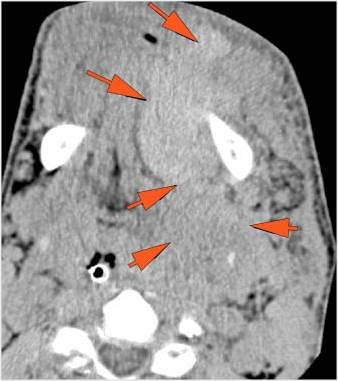

Facial and Scalp Soft Tissues and Airway

There is localized edema, hematoma or abscess within in the facial or scalp soft tissues, SMAS, infratemporal fossa, masticator space or oral cavity.

There is evidence of gas or a foreign body at a possible fracture site, indicative of an open or penetrating injury.

There is soft tissue swelling suggesting injury to the parotid or submandibular glands.